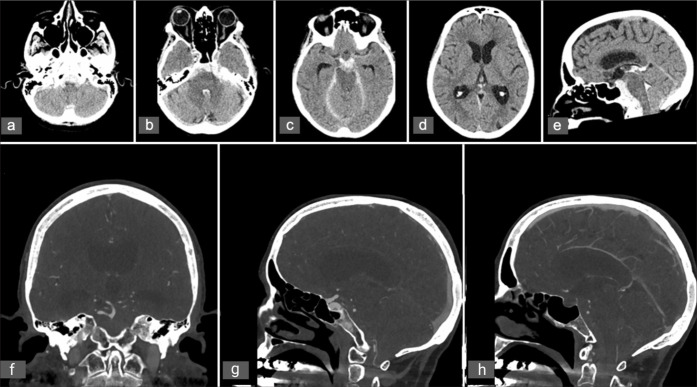

Case description: We present the case of a 77-year-old woman who experienced recurrent episodes of thunderclap headache, which eventually progressed to altered consciousness following admission. Neuroimaging revealed a SAH involving the fourth ventricle and basal cisterns, alongside cerebellar tonsillar herniation and obstructive hydrocephalus, with no arterial source identified on serial angiography. Magnetic resonance imaging confirmed CM1, with tonsillar descent to the C1 level. The patient underwent suboccipital decompression for refractory intracranial hypertension that prevented weaning from the external ventricular drain. Intraoperative exploration revealed an abnormal posterior spinal vein traversing the arachnoid membrane, which was suspected to be the source of the hemorrhage and was successfully coagulated.